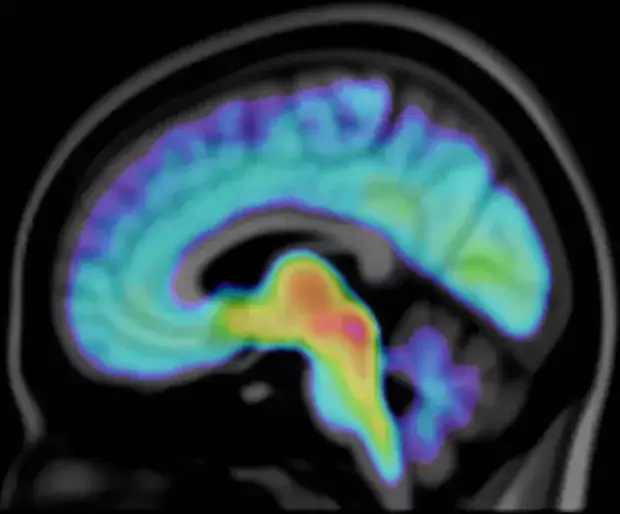

Photo: Illustration: Max Andersson.The Brain Molecular Imaging Centre (BMIC)

The Brain Molecular Imaging Centre (BMIC) is a Core Facility (CF) for molecular imaging of the brain using Positron Emission Tomography (PET). Our aim is to provide expertise and competence for brain imaging PET studies in human subjects and non-human primates (NHPs). BMIC supports research studies in psychiatric disorders, neurodegenerative disorders and neuropsychopharmacology, as well as a range of studies on other diseases and normal process in the brain or outside.